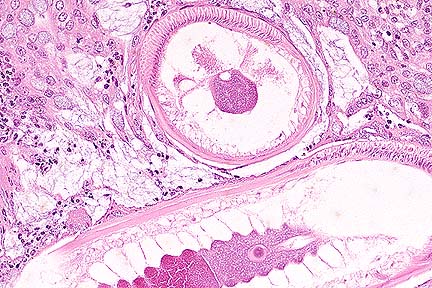

Lymphohistocytic hepatitis in an aborted foal. Note the eosinophilic intranuclear inclusion bodies within several degenerate hepatocytes. (HE, 400X, 75K)

Contributor's Diagnosis and Comments: Hepatitis, granulomatous, periportal, moderate, with rare random foci of hepatocellular necrosis and associated intranuclear eosinophilic inclusion bodies.

Equine herpesvirus-1 is an important cause of abortion in mares in addition to producing neurologic disease. Characteristic lesions in aborted foals are seen in the lung (necrosis of bronchial and alveolar epithelial cells, fibrinous alveolar exudation), liver (multifocal hepatocellular necrosis, periportal hepatitis), and lymphoid tissues (necrosis of germinal centers).ý Intranuclear inclusion bodies are seen in bronchial and alveolar epithelial cells, hepatocytes, and fixed and infiltrated macrophages. In this case, necrosis with accompanying inclusion bodies were seen in the liver, spleen, thymus, lung, and adrenal glands. In liver sections, intranuclear inclusions were most common in hepatocytes bordering necrotic foci and in infiltrated macrophages.

AFIP Diagnosis: Liver: Hepatitis, necrotizing, acute, multifocal, random, moderate, with lymphohistiocytic perivascular inflammation, and eosinophilic intranuclear inclusion bodies, thoroughbred, equine.

Mares that abort seldom show premonitory signs and the fetus is aborted in a fresh state; 95% of abortions occur in the last 3 months of gestation. The aborted fetuses often have subcutaneous edema and effusions in body cavities. The most consistent gross lesion is severe pulmonary edema. The lungs, renal cortices, and liver frequently have multifocal areas of necrosis and hemorrhage. Histologically, there is edema, hemorrhage, and necrosis multifocally throughout the lung and liver. Necrosis of germinal centers in the spleen, thymus, and lymph node is common. Intranuclear inclusions can be found in respiratory epithelium, hepatocytes, and cells of the monocyte-macrophage system. The placenta is normal in alphaherpesviral abortions.